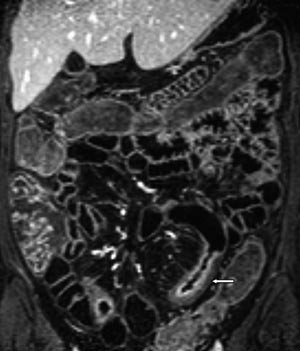

Vår erfaring med MR av tynntarm med oral kontrast er at metoden gir en god utvidelse av ileum. Bulbus duodeni er også ofte væskefylt, men det er vanskeligere å få resten av duodenum og proksimale jejunum optimalt utvidet (fig 3). En annen ulempe med MR av tynntarm med oral kontrast er ventrikkelretensjon (fig 4). Dette hemmer væskefylling av tarmen, og pasientene kan bli kvalme.

Vanlige MR-funn ved Crohns sykdom er fortykket tarmvegg (fig 5). Mer overflatiske forandringer i slimhinnen blir ikke optimalt fremstilt, men dypere ulcuser blir fremstilt, og dette er tegn på aktiv inflammasjon (fig 6). Både fibrose og aktiv inflammasjon i tarmveggen lader opp etter intravenøs kontrast. Det typiske for aktiv inflammasjon er en kraftig og lagdelt kontrastoppladning (fig 7), men den kan også være mer homogen.